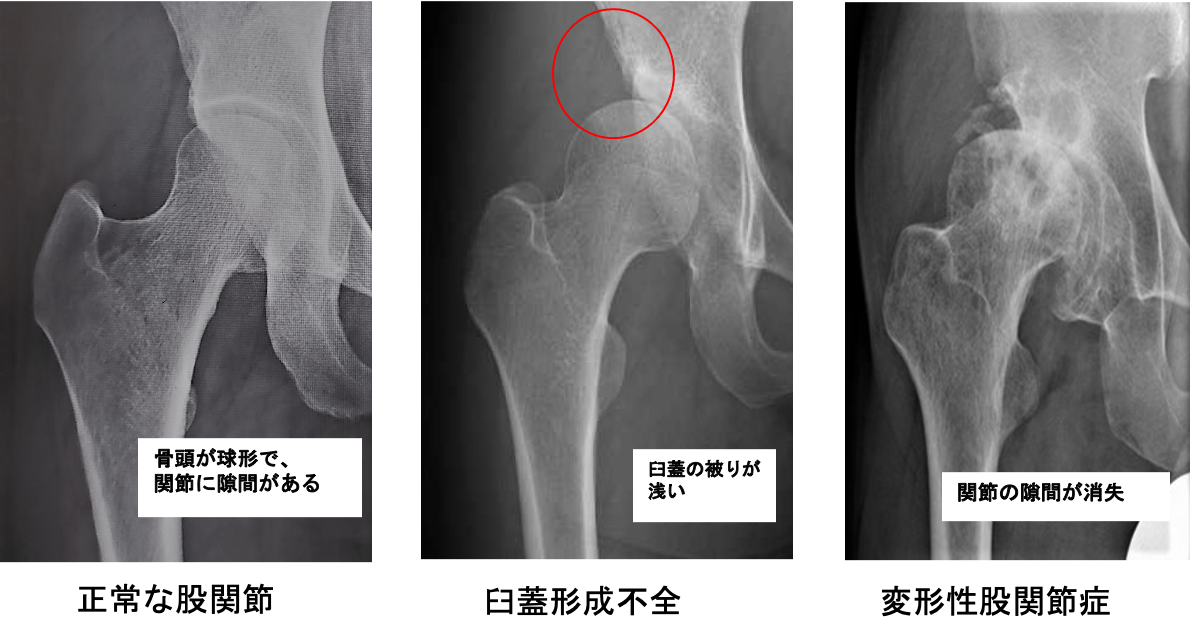

股関節の軟骨がすり減ることで痛みが生じる病気で圧倒的に女性に多いのが特徴です。骨の形の異常から二次的に発症するものがほとんどで、幼少期の股関節発育不全(臼蓋形成不全)のために骨盤側の受け皿の部分が浅いことが原因です。

股関節の中心である大腿骨頭が壊死してつぶれるために痛みを生じる病気です。アルコールの多飲やステロイドの使用に関連しているとも言われていますが、いまだにはっきりしておらず国の難病に指定されています。進行すると大腿骨頭が陥没を起こし、歩行が困難になります。症状が強ければ人工股関節置換術が必要になることがあります。